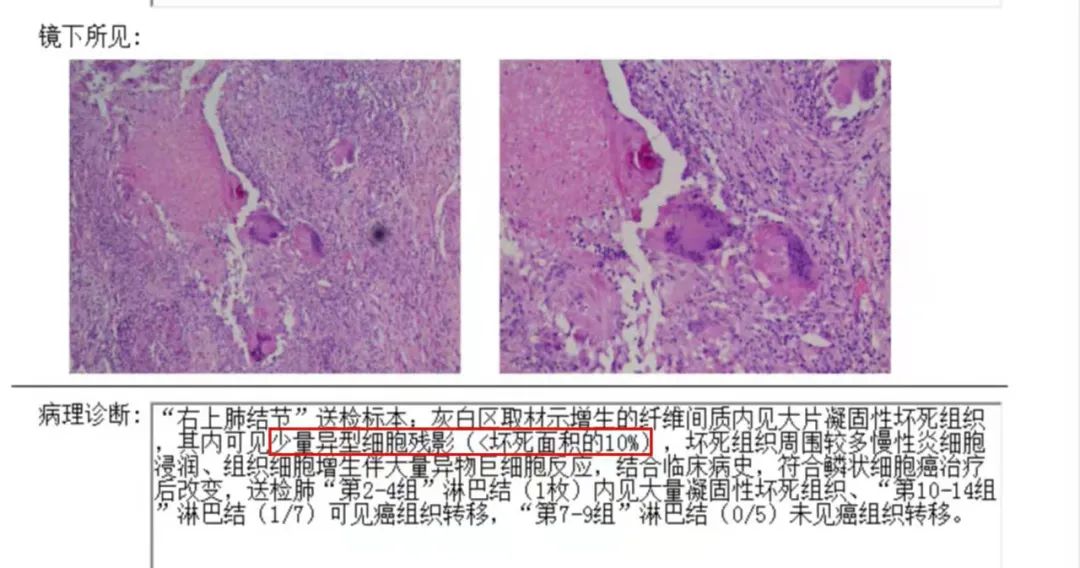

没想到我这么大岁数,切掉一个肺叶的十年后,再次做这么复杂的手术还这么顺利。 D大爷今年72岁,10年前曾行左肺上叶切除+淋巴结清扫术,手术标本病理为腺癌,术后给予了四次化疗。当时的胸部CT即可见右肺上叶小结节影,术后定期复查,病灶缓慢增大,一度略有缩小,此后再次逐渐增大。结合患者一直随访的影像学资料,杨如松院长考虑为右上肺新发恶性肿瘤。 2015年胸部CT 2020年胸部CT 虽然患者及其家属手术的意愿非常强烈,但此手术难度较高,原因在于: 1.患者年龄较高,手术风险大。 2.患者10 年前肺癌手术切除左边肺的一半,肺功能丧失较多。 3.病灶在右上肺的深部,切除有一定的难度。 为了保证患者术后的生活质量,我们不能够做肺的楔形切除这样的简单肺手术,而需要行肺段的切除。 EDDA重建提示病灶位置深 如果放在以前该患者就只能做做放化疗等保守治疗了。幸亏南京胸科医院目前引进了各种国内乃至国际上的先进技术。 如EDDA术前三D成像技术;只有单一3cm长切口的单孔胸腔镜技术;近红外荧光镜肺段、亚肺段精准定位技术等。 有了这些技术,杨如松院长心中有了底气。杨院长根据病人的情况设计手术方案,尽量减轻手术创伤,让接受第二次肺部复杂手术的高龄病人能够耐受,并且在术后能够顺利恢复。 根据术前EDDA三维重建,患者进行了单孔荧光胸腔镜S1a+2a切除术,术中先用ICG反染法确定段间面,再用膨胀萎陷法印证段间面,这保证了手术切除的精准性。 患者术中快速病理为贴壁型腺癌,这也印证了杨如松院长术前对患者肺结节良恶性的判断。 术后5天,D大爷非常顺利的出院了。出院前开心的窦大爷连声感谢杨如松院长:没想到我这么大岁数,切掉一个肺叶的十年后,再次做这么复杂的手术还这么顺利,谢谢、谢谢! 基本情况

手术方案